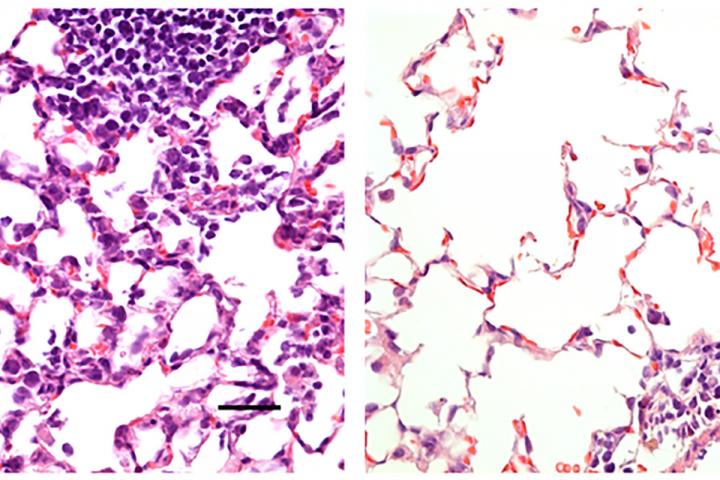

Researchers at Washington University School of Medicine in St. Louis have developed a COVID-19 vaccine delivered via the nose that protects mice from the virus. Shown is mouse lung tissue infected with SARS-CoV-2, the virus that causes COVID-19. On the left is lung tissue from a mouse that received a control vaccine that produced no protective effects. It shows a large number of inflammatory cells. On the right is lung tissue from a mouse that received a nasal vaccine encoding the virus' spike protein. The vaccine protected against infection, and large numbers of inflammatory cells are absent.